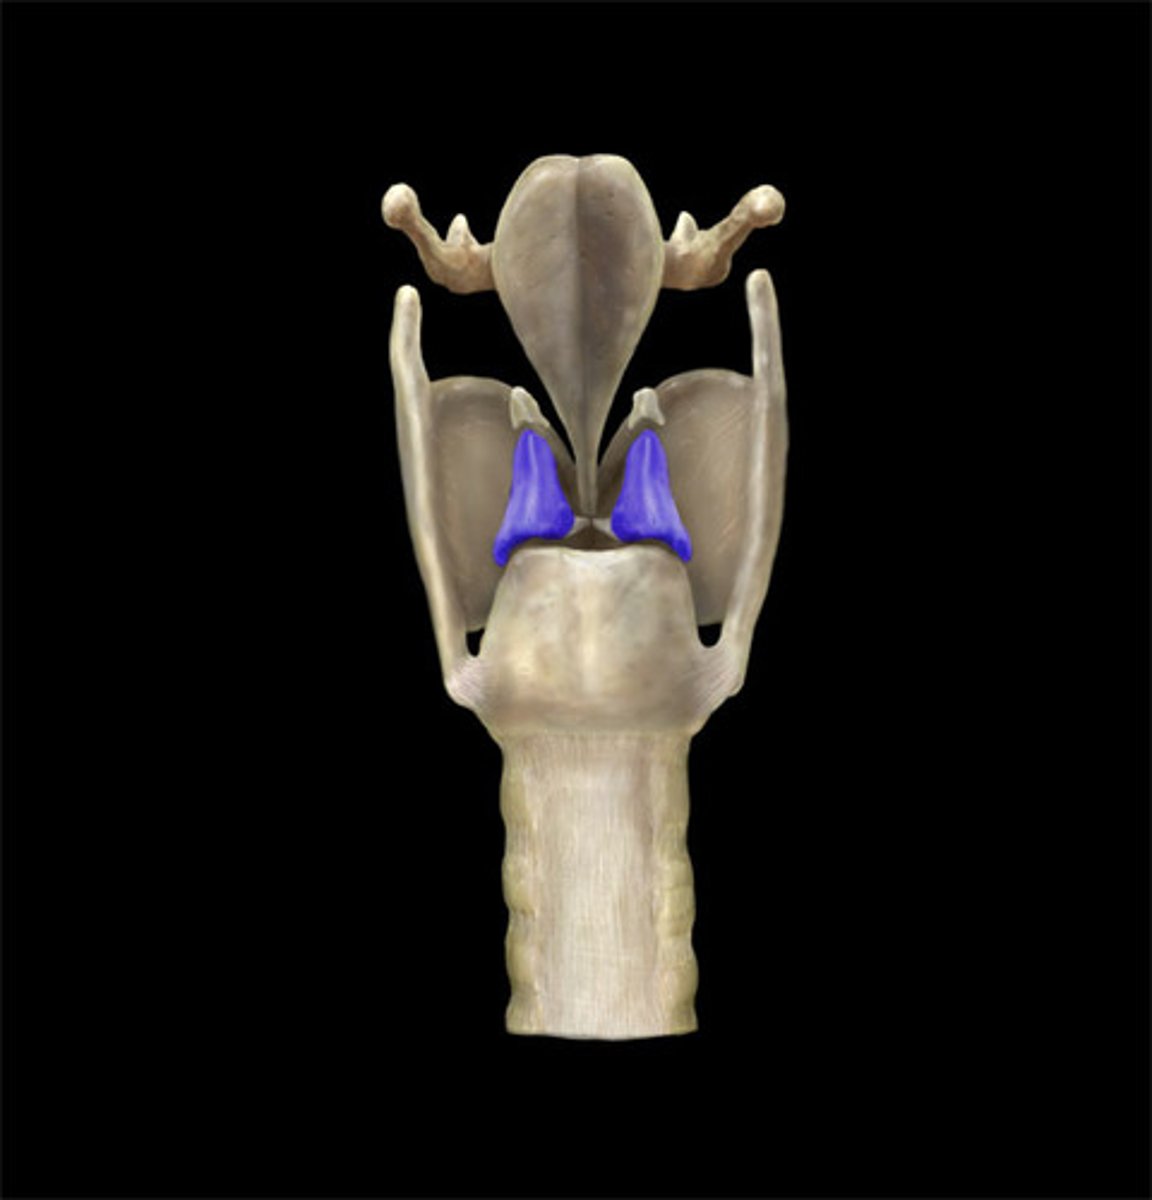

thyroid cartilage

cricoid cartilage

arytenoid cartilage